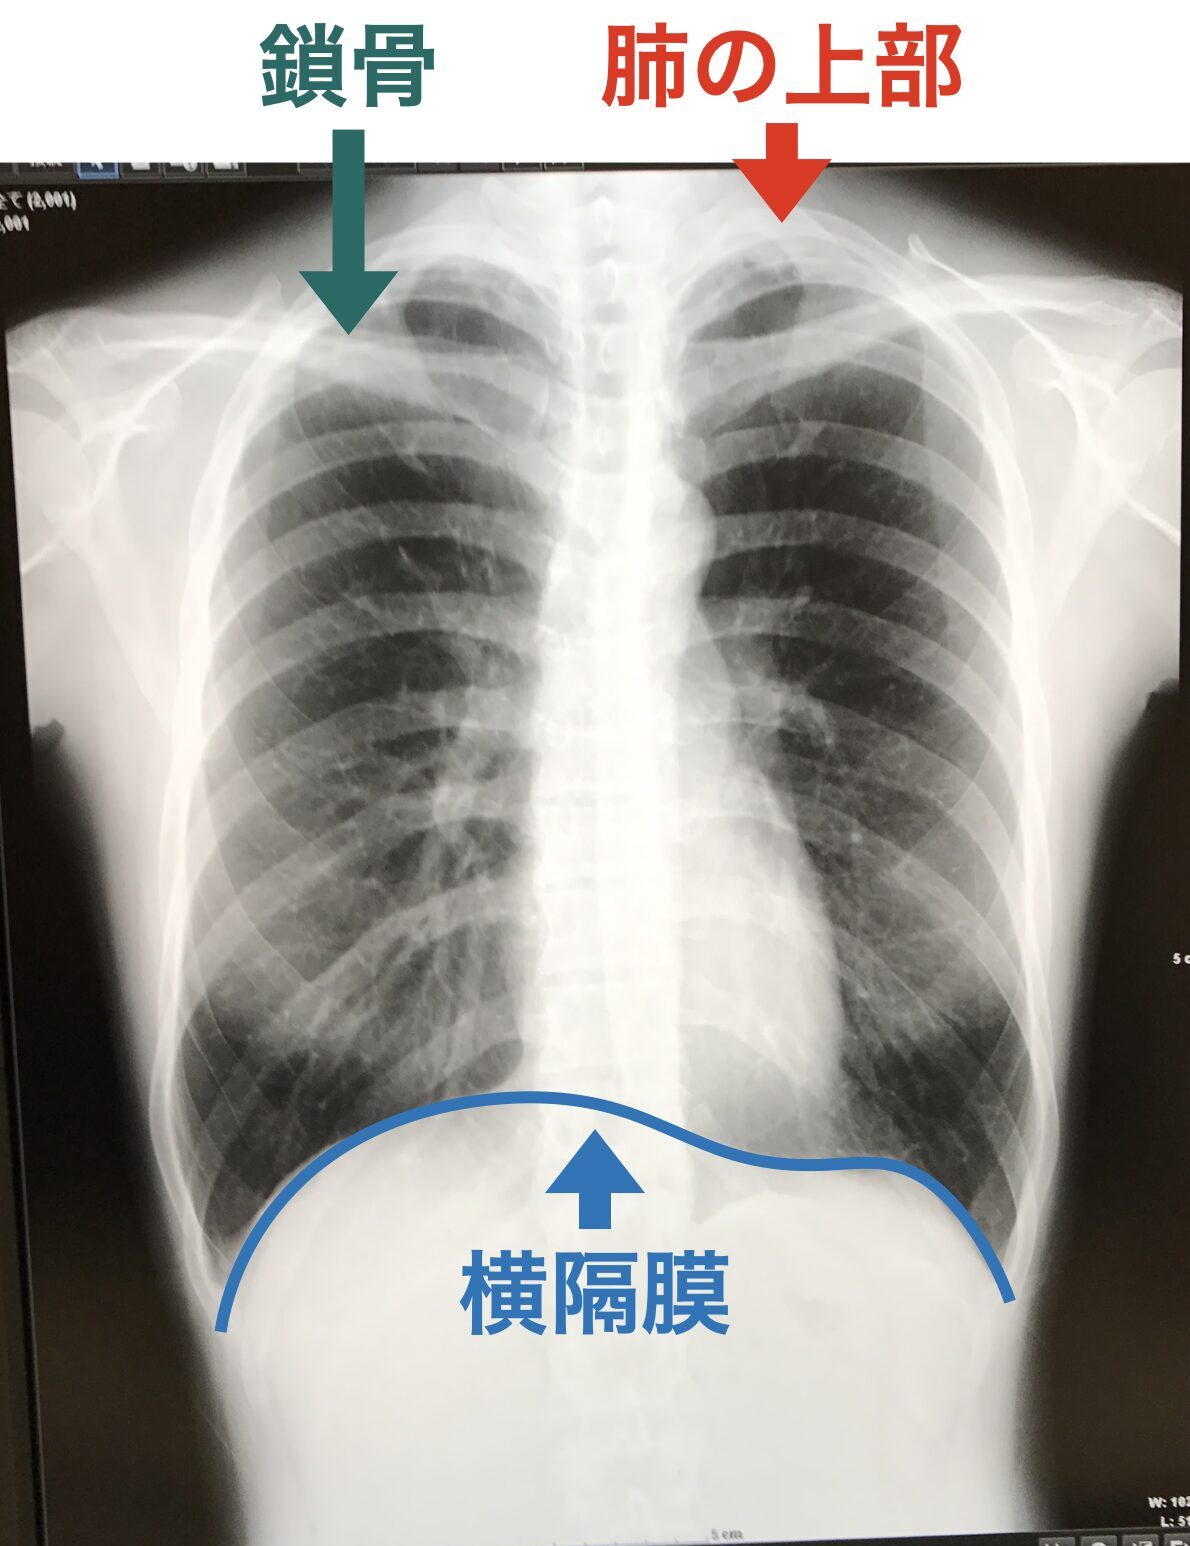

肺というのは横隔膜のすぐ上から、鎖骨よりも上まである大きなものです。

クラリネット奏者である筆者(有吉尚子)が健康診断で撮ったレントゲン写真が分かりやすかったので公開します。

鎖骨の上ということはいわゆる「肩」の高さにも肺はあるということ。

そこで上げてしまわないように肩の引き下げを行うと、空気を吸い込む動作の邪魔をしてしまうことになります。

身体が膨らむにつれて肩も上がるというのは、実は自然なことなのです。